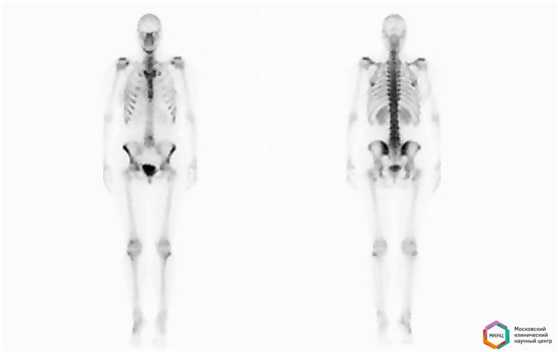

Остеосцинтиграфия - метод диагностики, основанный на введении в организм пациента препарата, который быстро и легко накапливается в костной ткани и содержит в своем составе изотоп (общее название - радиофармпрепарат). Вспышки излучения, который испускает изотоп, фиксируются затем с помощью специальной гамма-камеры. Этот метод позволяет изучить сразу весь скелет в отличие от рентгеновских снимков, на который имеется изображение отдельных костей. Остеосцинтиграфия является основным способом ранней диагностики первичных опухолей и метастатических поражений скелета, оценки эффективности проводимого лечения после химиотерапии и лучевой терапии злокачественной опухоли, а также дифференциальной диагностики опухолевого и воспалительного поражения костей.

Суть метода состоит в том, что пораженая костная ткань накапливает радиоактивные изотопы гораздо быстрее, чем здоровая. В итоге на изображениях паталогическиеочаги в костях будут иметь вид зонповышенного или пониженного накопления (черный и белый цвет). Отмечено, что метастазы могут быть обнаружены с помощью остесцинтиграфии значительно раньше, чем при выполнении других исследований.

Подготовка не требуется, исследование проводится в двух проекциях, передней и задней в режиме всего тела, через 2 - 2,5 часа после внутривенного введения препарата.Перед исследованием пациенту внутривенно водят небольшую дозу радиофармпрепарата, содержащего изотоп технеция Тс99 и способного накапливаться в костной ткани, затем оценивают его распределение с помощью гамма-камеры и серии сцинтиграмм.